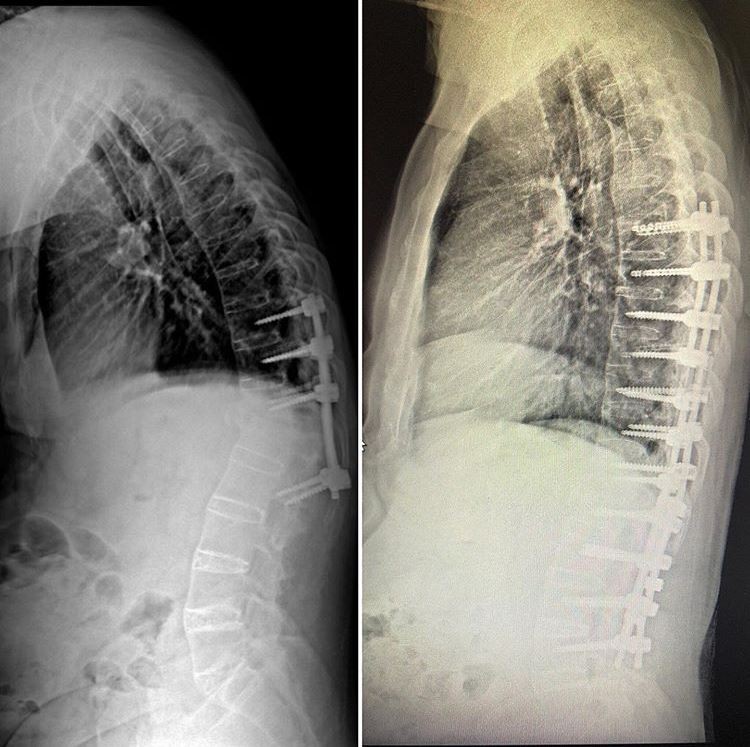

Manisa Şehir Hastanesi Beyin ve Sinir Cerrahi Kliniğinde skolyoz ve kifoz ameliyatları başarı ile gerçekleştirilmeye başladı. Manisa’da M.E. (63) isimli yaşlı adam 6 ay önce geçirdiği trafik kazası sonrası omurgasında oluşan kırıklar nedeniyle başka bir şehirde ameliyat oldu. Aradan geçen 6 ay içinde yaşlı adamın omurgasında öne doğru kamburluk, solunum sıkıntısı ve yürüme bozukluğu başladı. Manisa Şehir Hastanesine müracaat eden yaşlı adam yapılan tetkiklerin ardından Beyin ve Sinir Cerrahi Hekimi Op. Dr. Ülkün Ünlü Ünsal tarafından ankilozan spondilit tanısı ile ameliyata alındı. Yapılan başarılı operasyonun ardından yaşlı adamın hem kamburluğu giderildi hem de yeniden sağlığına kavuştu.

Ameliyat hakkında bilgi veren Manisa Şehir Hastanesi Beyin ve Sinir Cerrahi Hekimi Op. Dr. Ülkün Ünlü Ünsal, “M.E. 63 yaşında ve halk arasında Ahmet Mete Işıkara Hastalığı olarak da bilinen Ankilozan Spondilit tanılı hastamız, 6 ay önce geçirmiş olduğu trafik kazası sonrası omurgasında T12-L1 kırık oluşmuş ve dış merkezde ameliyatı gerçekleştirilmiş. Aylar içinde omurgasında öne doğru oluşan kamburluk (kifoz) meydana gelmiş. Omurgasındaki eğrilik nedeni ile duruş bozukluğuna bağlı solunum sıkıntısı ve yürüme bozukluğu yaşamaya başlayan hasta M.E. Manisa Şehir Hastanesi Beyin ve Sinir Cerrahi Kliniğine başvurmuş gerekli tetkikleri yapılmış, gerçekleştirilen başarılı ameliyat sonucunda omurgasındaki eğrilik giderilerek sağlığına kavuşmuştur. Hastanemizde cerrahi tedavi olarak omurga tespit sistemleri ve ameliyatları ücretsiz olarak yapılmaktadır” dedi.